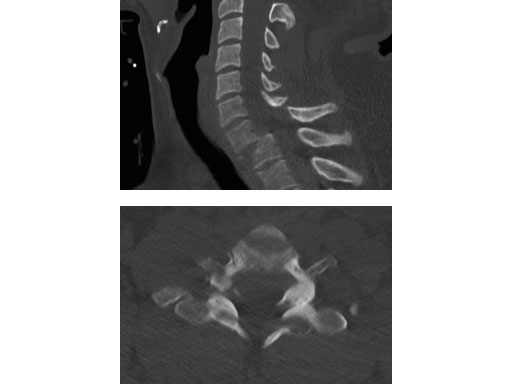

A 28-year-old, 109 kg man was involved in a high-speed motor vehicle collision with C7-T1 jumped facet and T1 teardrop fracture. The patient had ASIA E with motor score of 100. He had failed closed reduction in the emergency room then was taken to OR emergently for open reduction and C5-T2 posterior segmental instrumentation with synapse 4.0. The patient did well postoperatively with no evidence of collapse or failure.

Synapse 4.0 was the ideal solution to treat this injury. This was a heavy patient with a highly unstable injury at the cervicothoracic junction. Synapse 4.0 enabled stabilization of his injury with a rigid construct. It has all the benefits of the 3.5 system but is more rigid and allowed use of one system as opposed to using the 3.5 system and a 6.0 rod system with the nuances of a tapered rod. The author was able to place C5 and C6 lateral mass screws utilizing the Magerl technique and C7, T1, and T2 pedicle screws.